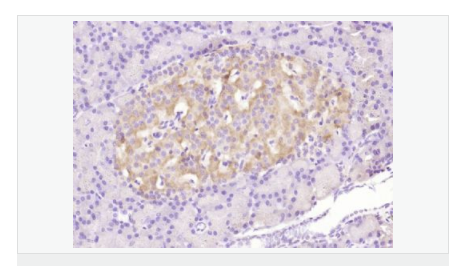

產(chǎn)品應(yīng)用WB=1:500-2000 ELISA=1:5000-10000 IHC-P=1:100-500 Flow-Cyt=3μg /test (石蠟切片需做抗原修復(fù))